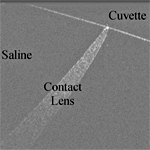

Application of optical coherence tomography to automated contact lens metrology

B. R. Davidson, et al., Journal of Biomedical Optics, 15 (1), 2010.

Link